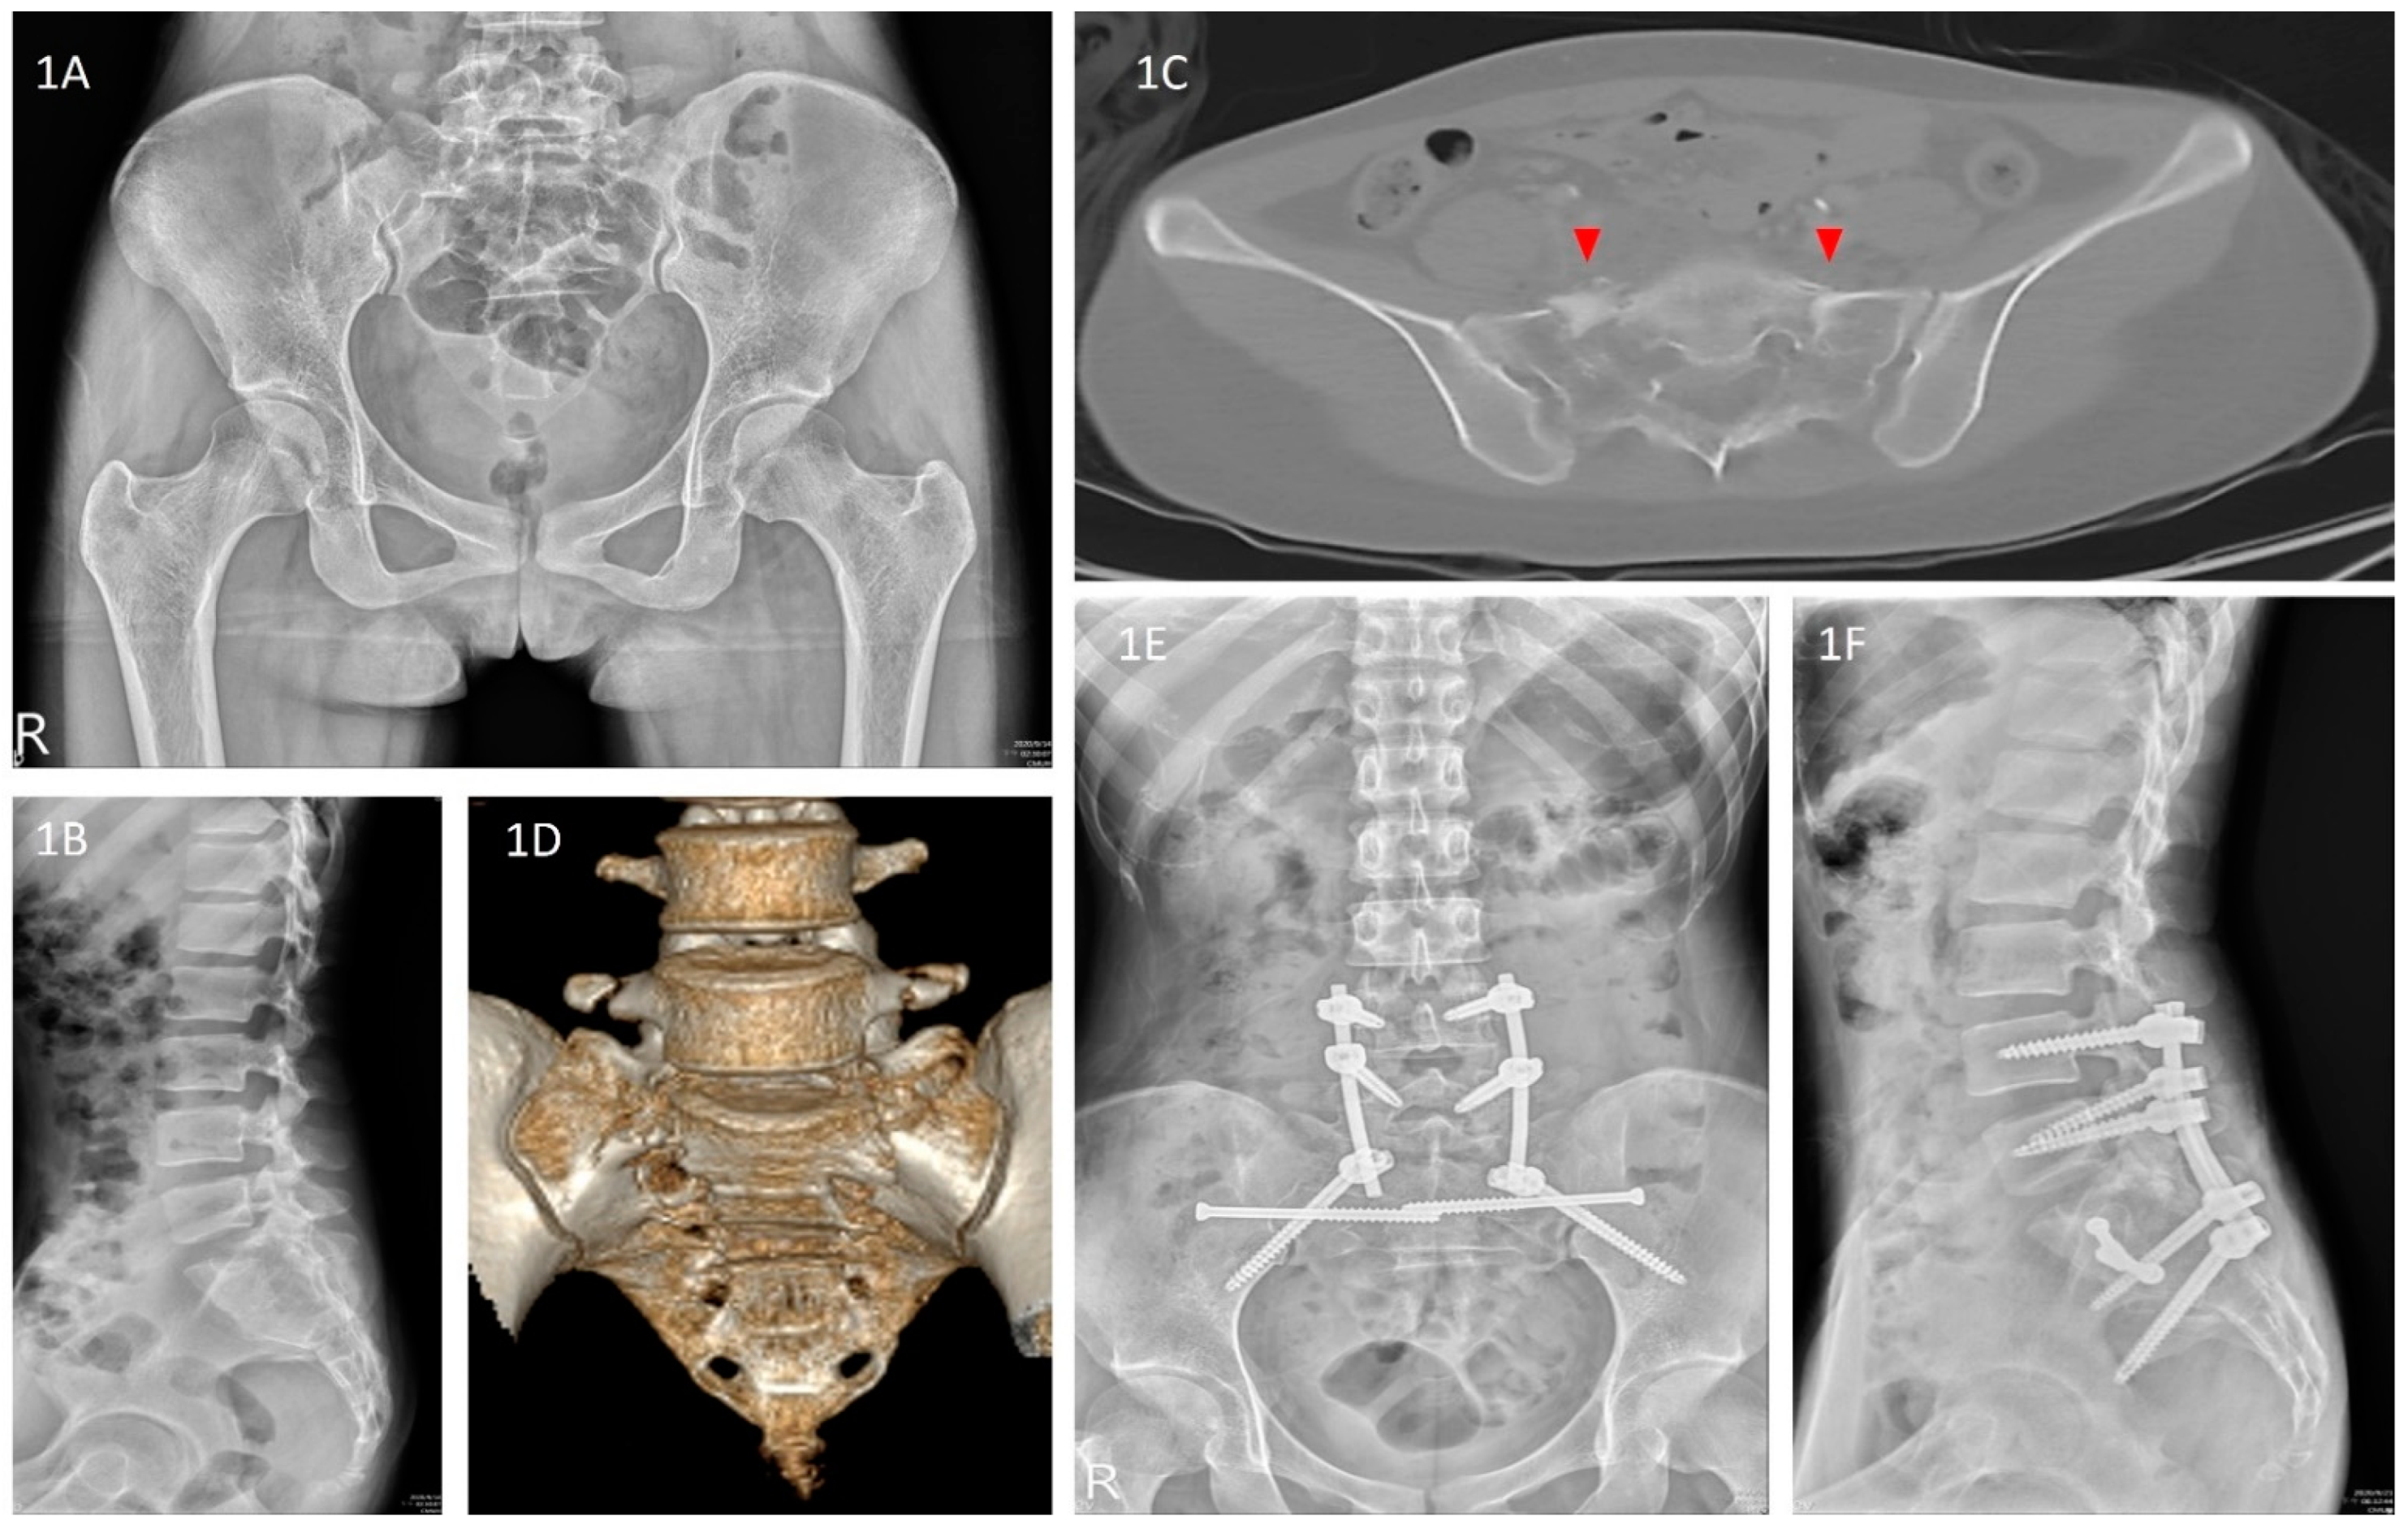

| Lefaivre et al., 2009 | Absolute displacement method (ADM) [13] | This method was initially proposed by Lefaivre et al. in 2009. Observers were instructed to use preoperative pelvic AP, inlet, and outlet views. In each view, a horizontal line was drawn across the superior end plate of L5 as a reference line. If this was not visible in the film, the observers were asked to use the inferior end plate of L5 as a reference. Measurements were either parallel or perpendicular to this reference line. This line was used as the direction for horizontal measurements, or a line 90 degrees to this reference line was used for vertical measurements. Maximum displacements in the anterior and posterior pelvic rings were measured in each plane film. After completing the six measurements of the three preoperative films (anterior and posterior rings in each of the AP, outlet, and inlet views), the observers were instructed to measure the same anatomic locations in the postoperative plane films. Finally, the largest single measurements from the six preoperative and postoperative measurements were considered the preoperative and postoperative maximum displacements, respectively (Figure 5A,B). |